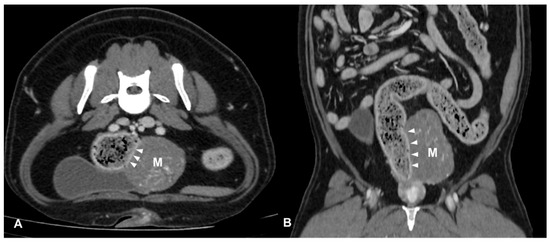

CT identified a colorectal lesion in all dogs. Specifically, 5 dogs had lesions localized at the colorectal junction, 3 at the descending colon, 1 at the transverse colon, and 1 at the anorectal junction. The characteristics of these lesions varied: 6 (Figure 1) dogs exhibited transmural, circumferential, asymmetric thickening of the wall, while 2 (Figure 2) cases (one adenocarcinoma and one carcinoma) displayed transmural, circumferential symmetric thickening. The leiomyosarcoma case was characterized by the presence of an exophytic mass (Figure 3).

Luminal stenosis was noted in all cases except for two: the descending colic leiomyosarcoma and the colorectal adenocarcinoma. In one case of anorectal squamous cell carcinoma, the infiltration of surrounding structures such as anal sacs and tail muscles was observed. Additionally, adherences between the lesion and surrounding structures like the urinary bladder, sacro-caudal muscles and epaxial muscles, tail of the spleen, and/or left external iliac artery were noted in 4, 3, and 1 dog, respectively.

Figure 3. Post-contrast CT images of a colic mesenchymal tumor (leiomyosarcoma) in an 11-year-old mixed breed neutered male dog. Transverse (A) and dorsal (B) plane reconstructions are available. An expansile, heterogeneously enhancing soft tissue opacity lesion (M) is seen in continuity with the left lateral wall descending colon (arrows heads). The mass is exophytic and involves the outer layer of the colic wall. Multiple mineral foci are observed within the lesion.